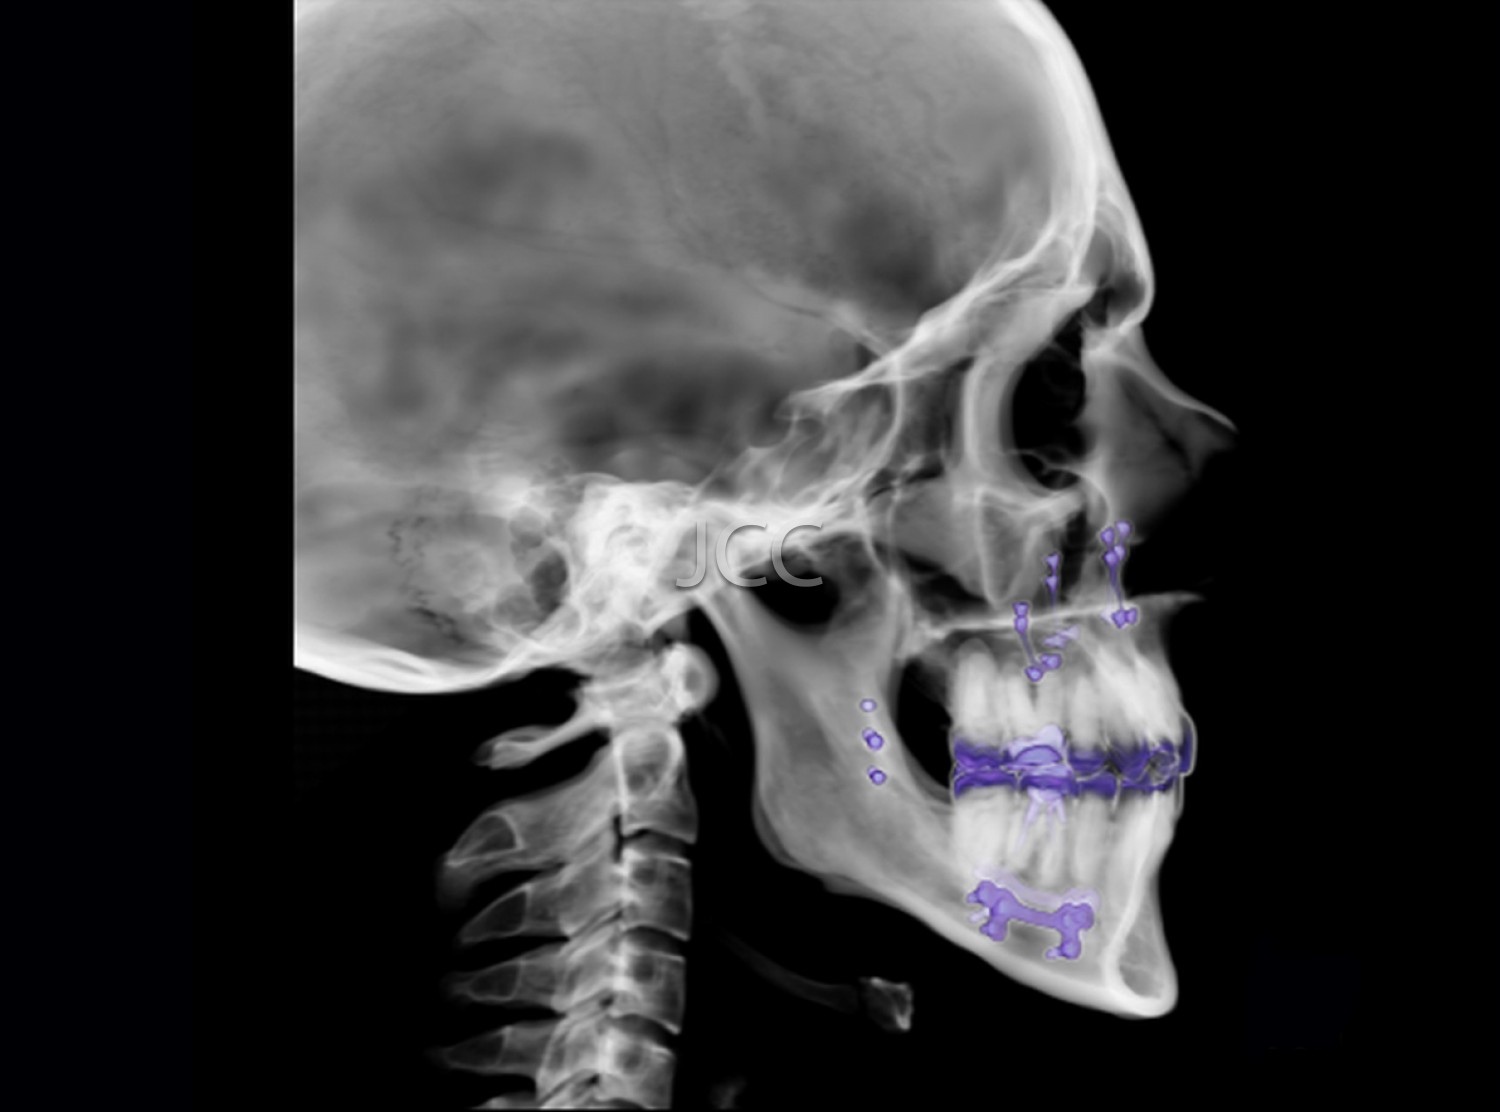

Dental Radiology - Maxillofacial CBCT / CT

Applications

• Orthognathic surgery

• Maxillofacial Surgery and Traumatology